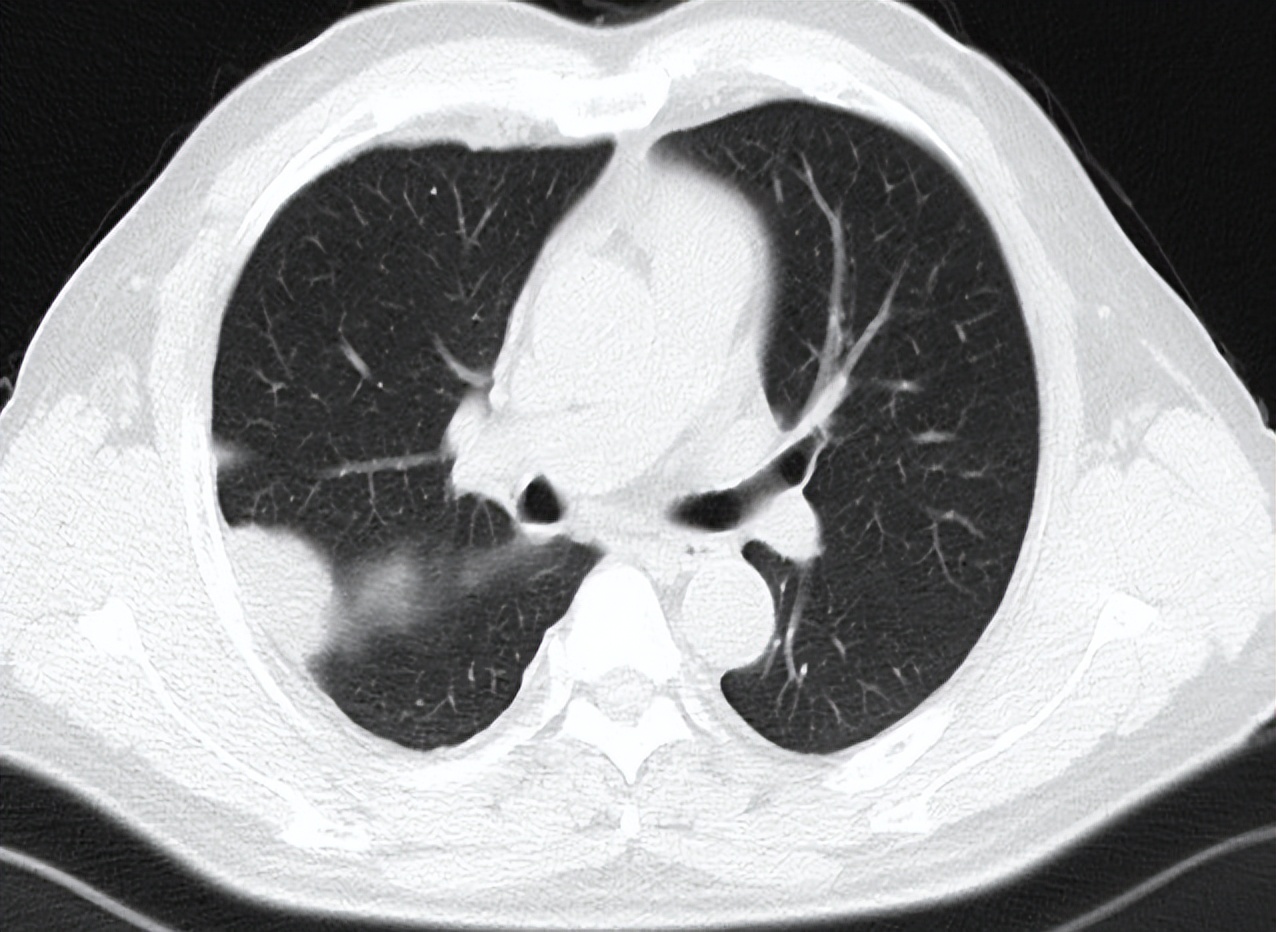

患者男性,56岁,因反复咳嗽入院 2016.12.22行胸部CT检查提示:右侧胸膜为广泛增厚呈不规则状、结节样的增厚,右侧胸腔可见有大量的胸腔积液。纵隔、肺门淋巴结不大,考虑胸膜间皮瘤可能。于2017-1-10行VATS右胸膜活检术,术后病理提示(右胸膜)恶性肿瘤,结合酶标结果考虑恶性间皮瘤。免疫组化结果:TTF-1(-),NapsinA(-),CK7(+),WT-1(+),CK5/6(+),CAL(+),MC(+),D2-40(+)。术后恢复良好,术后予抗炎、补液等对症治疗,诊断为:右侧胸膜间皮瘤cT4N1M0-IIIB期。患者于2017-2至2017-5行AP(培美曲赛联合顺铂)方案化疗共4周期。2017-6-27胸部CT检查提示疗效部分缩小(PR)。

考虑到胸膜间皮瘤当时并没有维持治疗的临床研究结果,借鉴非小细胞肺癌维持治疗的研究数据,给予培美曲赛维持化疗,共25周期。